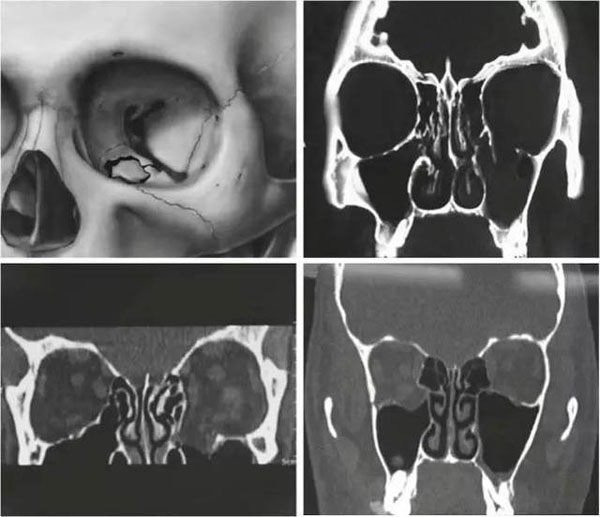

近年來,隨著工業外傷和交通事故發生率的增加,眼眶骨折的患者越來越多。眼眶壁骨質薄弱,發生骨折后容易產生骨質缺損,需要使用生物材料替代缺損的骨組織,來重建眼眶結構。

自1990年鈦網首次成功應用于眼眶修復以來,鈦網作為填充和內固定材料被應用于眶壁、眶底缺損的修復。但鈦網不規則的形狀和光滑的表面容易被纖維組織包裹,有促進炎癥細胞高密度分布和粘連的可能,并且會引起鄰近骨質的溶解。

由于鈦網邊緣銳利且具有一定硬度,當手術切口較小時,鈦網容易被周圍組織阻礙,難以插入預定的位置,在插入的過程中甚至容易造成醫源性損傷。此外,由于鈦網較薄,無法糾正眼眶與面中部骨折后期容易發生的眼球內陷。